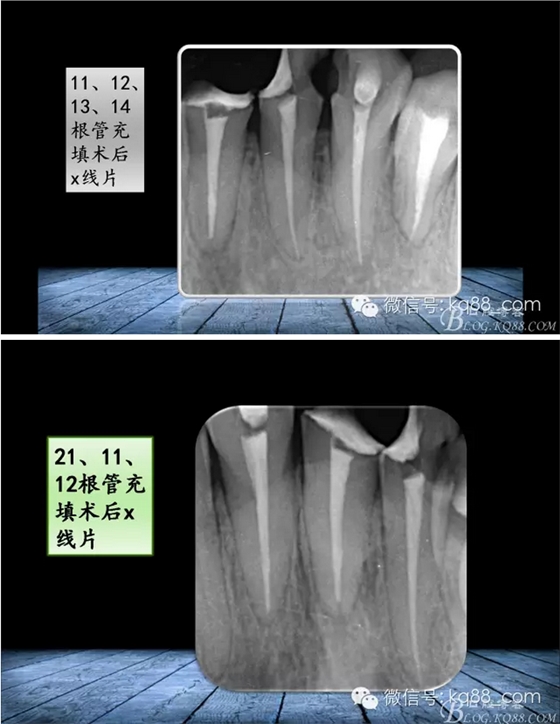

QQ圖片20150817140731.png

QQ圖片20150817140748.png